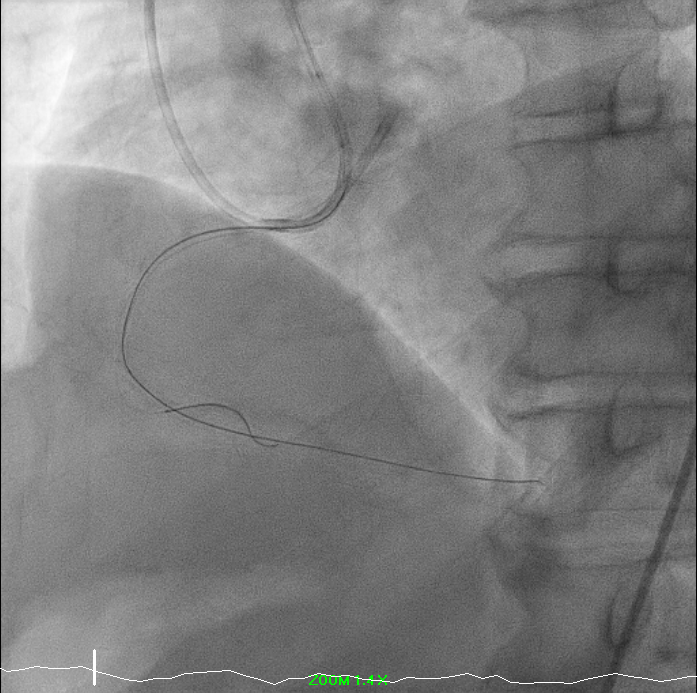

PCI to RCA CTO ISR: A PCI was performed for RCA chronic total occlusion in-stent restenosis (ISR) in a patient with ischemic cardiomyopathy, reduced LVEF, and moderate inducible ischemia. Femoral access was obtained using EBU (USG-guided, single attempt) and RRA 7F exchange. Initial crossing attempt with Corsair Pro XS/Fielder XTR failed; the lesion was successfully crossed using Fielder XTA, confirmed by retrograde angiography. Microcatheter was removed using the balloon trapping technique.